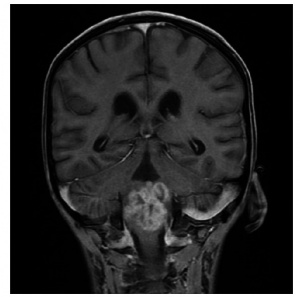

Monocular nystagmus of childhood

Monocular nystagmus of childhood is nystagmus that involves the same eye at all times in a child. The waveforms have small amplitudes and can be vertical or elliptical. Heimann-Bielschowsky phenomenon is a type of monocular nystagmus that occurs due to longstanding poor vision in one eye with amblyopia, optic neuropathy, or dense cataract. It can often be inhibited by convergence or fixation. There are reports of improved monocular nystagmus after extraocular muscle surgery in the case of strabismic amblyopia causing the Heiman-Bielschowsky phenomenon.[24][25] When an infant presents with signs of afferent pathway disease (eg, optic disc atrophy, relative afferent pupillary defect, and monocular nystagmus) however, neuroimaging should be considered.[26] See Figure 3 for an example of a child who presented with monocular nystagmus and a chiasmic-hypothalamic mass.[27]